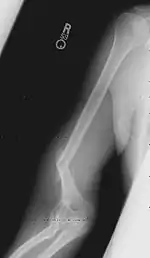

Травматизм

Кажущаяся простота движений создаёт у многих иллюзию доступности вида спорта. Вид спорта травмоопасен: нагрузки на локтевые и плечевые суставы, связки, кости предплечья и плеча очень велики. Для избежания подобных травм, принципиально употребление кальция для укрепления базы (костей), практика (искусственный оппонент на основе тренажёров) и общее укрепление, упираясь на укрепление жил/сухожилий для предотвращения разрывов мышц.